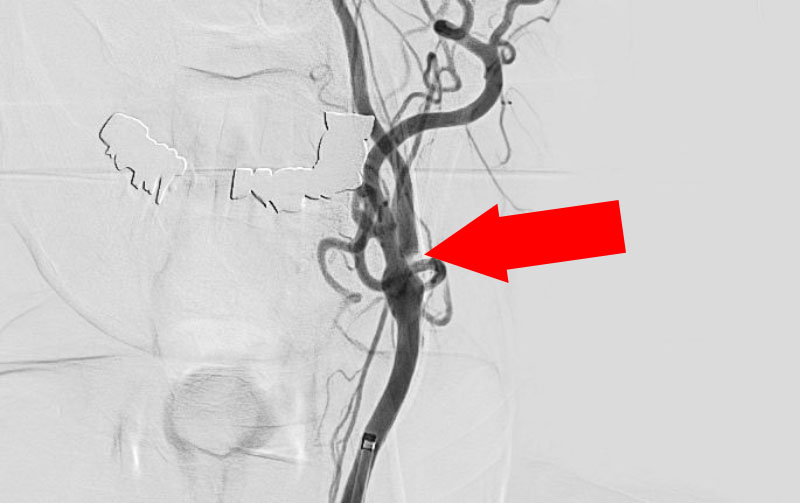

1222

'22年4月26日

左内頚動脈狭窄症

70代

院内外来

中

治療